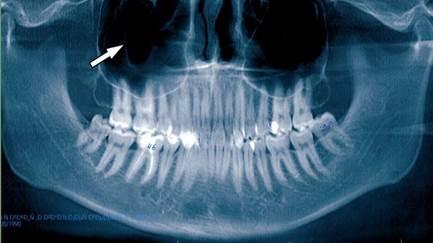

Рис. 1. Ортопантомограмма верхней и нижней челюстей. Стрелкой указано на пристеночное утолщение слизистой оболочки в правой верхнечелюстной пазухе.